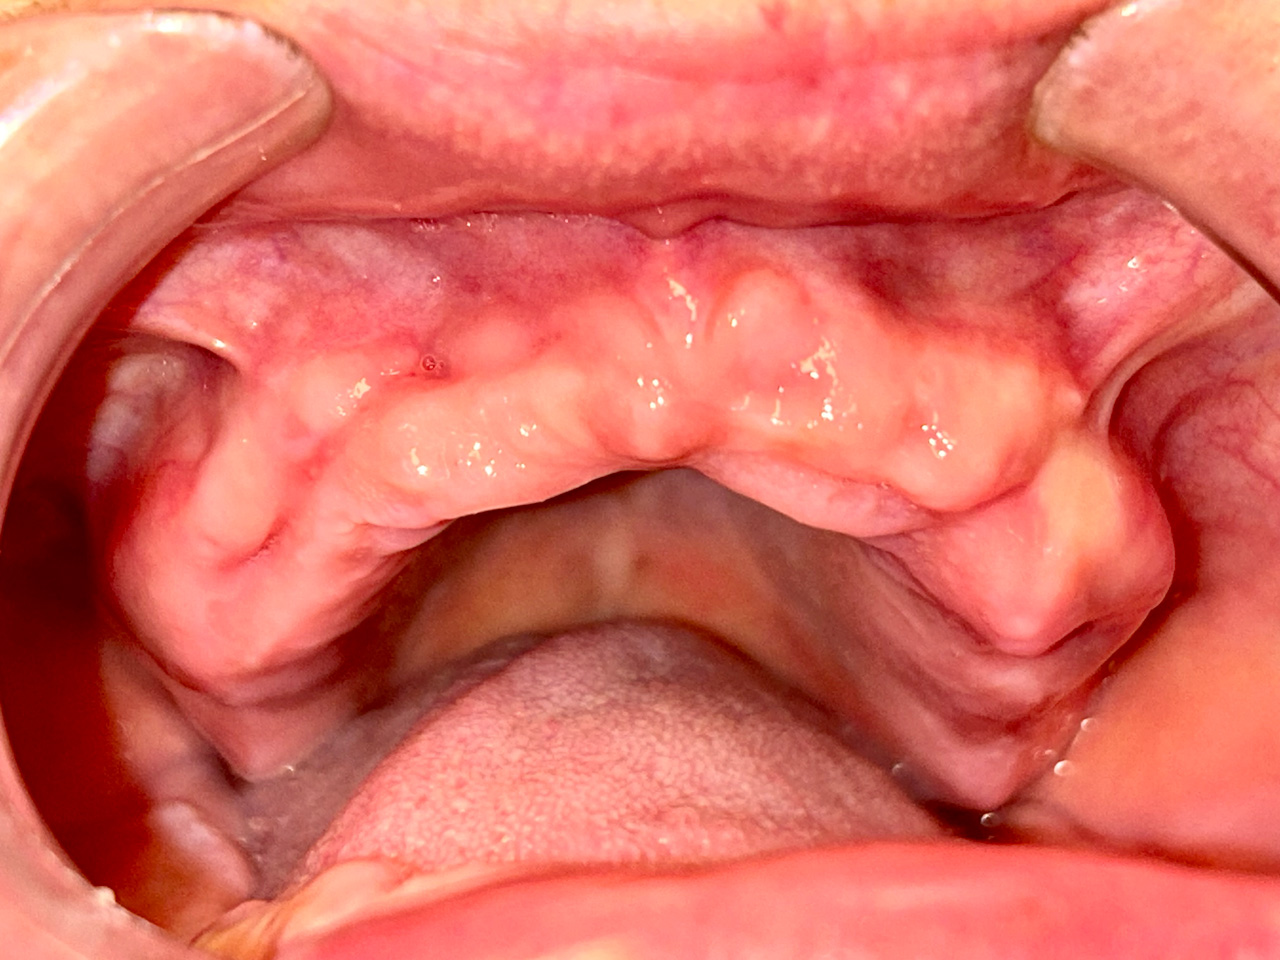

Teljes fogatlanság helyreállítása 2 nap alatt

Teljes fogatlanság helyreállítása 2 nap alatt azonnal terhelhető svájci IHDE implantátumokkal és PMMA műanyag hidakkal. Intraorális szkennerrel vettünk lenyomatot az implantáció után, és erre a digitális mintára készítette el a fogtechnika a hidak digitális tervezését, majd faragta ki műanyagból. Ezt a gyors munkát az azonnal terhelhető implantátumok és a digitális lenyomat, tervezés segítségével tudtuk megcsinálni mindössze 2 nap alatt. Dr. Kelemen Péter és a Symbion Fogtechnika munkája.